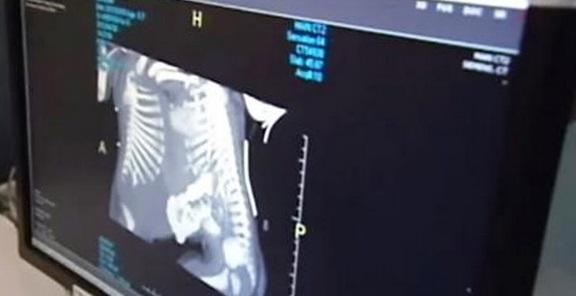

Όταν η Shellie Tucker έφτασε την 20η βδομάδα της εγκυμοσύνης της, την περίμενε μια μεγάλη έκπληξη. Αυτή και ο σύζυγος της, Greg, ενημερώθηκαν πως περίμεναν δίδυμα. Δεν ήταν, όμως, αυτό το μόνο που έμαθαν από το γιατρό!Ο υπέρηχος έδειξε πως τα μωρά ήταν ενωμένα στο θώρακα, το διάφραγμα, το ήπαρ και στη μεμβράνη γύρω από την καρδιά. Αυτό το γεγονός ήταν που τρόμαξε το γυναικολόγο ώστε να τους συμβουλεύσει να διακόψουν την εγκυμοσύνη.

Σύμφωνα με το CNN, το συνολικό ποσοστό επιβίωσης των συνδεμένων διδύμων είναι μεταξύ 5%-25%. Όσον αφορά τις επεμβάσεις διαχωρισμού, στο 75% των περιπτώσεων, επιζεί τουλάχιστον το ένα παιδί.Όλα αυτά, βέβαια, δεν ήταν ιδιαίτερα ενθαρρυντικά. Γι’αυτό και η διακοπή της κύησης φαινόταν μονόδρομος. Αλλά δεν ήταν.Παρά το σοκ της αποκάλυψης για τα παιδιά τους, οι δύο γονείς αρνήθηκαν να τα “σκοτώσουν”. Θέλησαν να τους δώσουν την ευκαιρία τους στη ζωή.Έτσι η Shellie γέννησε μετά από λίγο καιρό, με καισαρική, την Amelia κα την Allison. Και κάπως έτσι ξεκίνησε το ταξίδι για αυτά τα δύο κοριτσάκια…